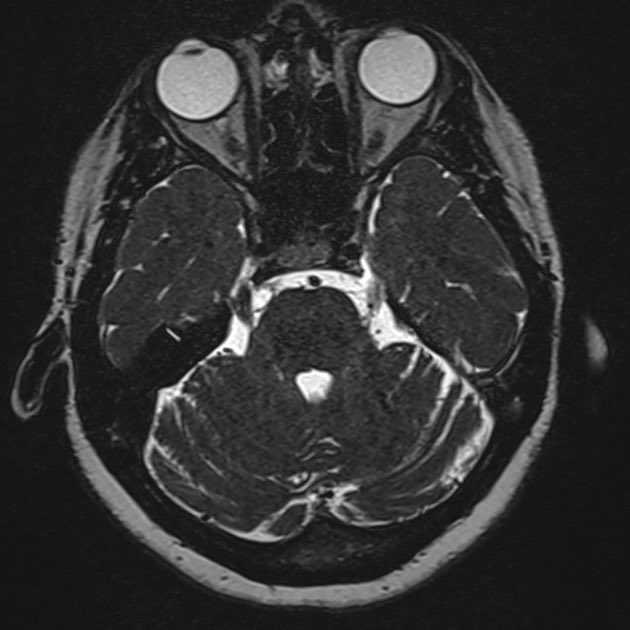

-الرنين المغناطيسي للدماغ